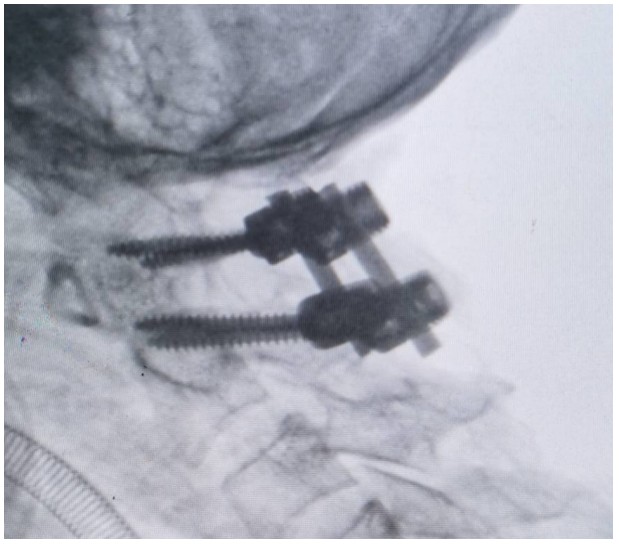

術(shù)中,錢軍博士團隊展現(xiàn)出了非凡的勇氣和精湛的醫(yī)術(shù)。他們精心準備,與手術(shù)室和麻醉科的同仁們緊密協(xié)作,以專業(yè)的技術(shù)和精確的操作,成功完成了這一高難度的手術(shù)。手術(shù)室外,譚女士的家人焦急等待,當(dāng)手術(shù)成功的消息傳來時,譚女士的家人不禁流下了感激的淚水。

術(shù)后,譚女士在骨科一區(qū)(脊柱外科)醫(yī)護人員的細心照料下,逐漸恢復(fù)活力,痛苦得到緩解,頸椎活動也日益靈活。譚女士的家屬對手術(shù)效果感到非常滿意,多次對醫(yī)護人員的精湛技藝和無私奉獻,當(dāng)面表達出深深的敬意和感激。